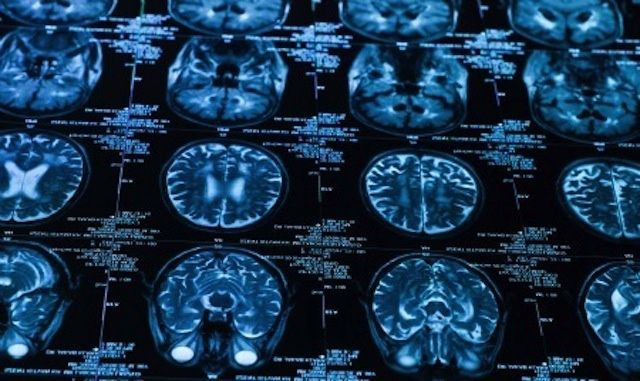

Examinations of this kind can only be performed on the brains of deceased athletes.

As we have covered in our previous reporting, this type of brain damage is more commonly known as Chronic Traumatic Encephalopathy (CTE).